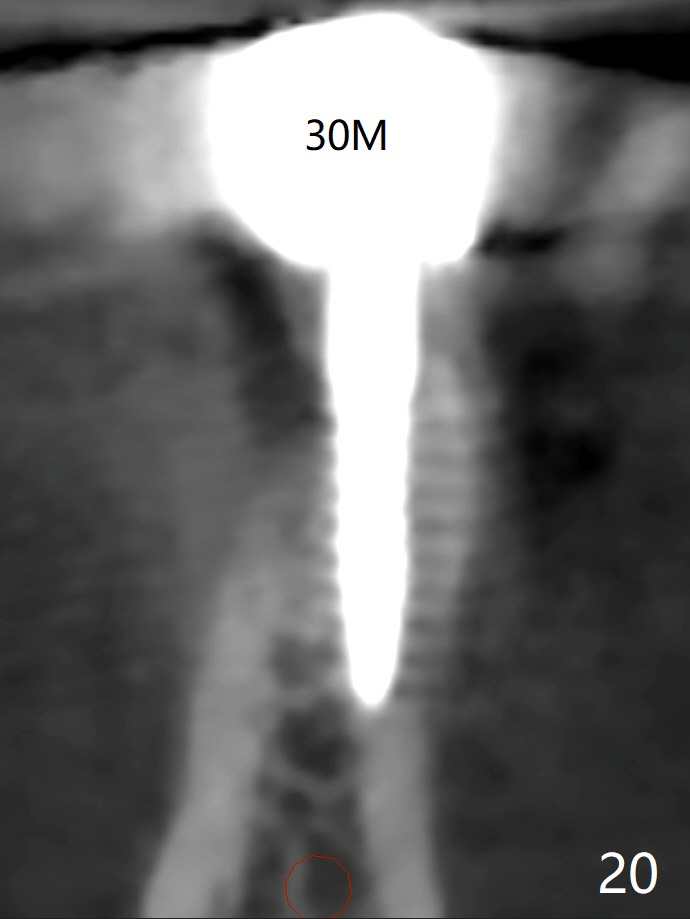

Two of 2.5 mm 1-Piece Implants M

The edentulous ridge at #30 is narrow (Fig.1). After ridge reduction, osteotomy is initiated with 1.2 mm drill for 10 mm; the mesial osteotomy is to be changed (Fig.2 red line). Using a 1.2 mm drill placed in the distal osteotomy (Fig.3 D), the mesial osteotomy changes in trajectory with subsequent placement of a 2.5x10(4) mm 1-piece implant. Since the mesial implant is high in occlusion, the cuff of the distal implant is changed to be 2 mm (Fig.4 (shorter black line)). Panoramic X-ray is taken to show no violation of the Inferior Alveolar Canal (Fig.5 red dashed line). These two 1-piece implants are slightly lingually placed (Fig.6). The crestal bone around the implants resorbs without thread exposure 5 months postop (Fig.7). Impression is taken for a splinted crown (Fig.8-12). There is no metal show around the 2.5 mm 1-piece implants 6 months postop (advantage) vs. that at #28 and 29 (Fig.13). Bitewing is taken post cementation to determine whether residual cement is present (Fig.14). There is periodic swelling and pain in the lower right quadrant 2 years post cementation (Fig.15). In fact periimplantitis appears to have developed at #28 (Fig.16) with loss of the buccal bone (Fig.17,18). The buccal bone loss is less at #29 (Fig.19) and #20 (Fig.23) and no at #30 mesial and distal implants (Fig.20,21). A much smaller implant will be placed lingually at #28 immediate (Fig.24,25).